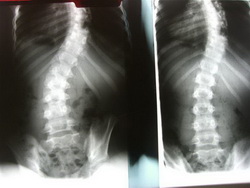

The aim of scoliosis surgery adults is to straighten the spine and preventing further curvature. This is done by bracing the spine with metal plates and usually grafting with a hip bone. It is believed that the scoliosis surgery adult's options are most successful at curvatures that are over 45 degrees. Surgery is only one of a number of treatments and in a lot of cases it won't be the recommended path to take.